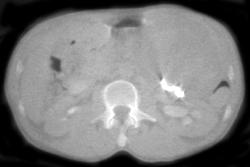

Pancreatic Cancer Involves the Duodenum